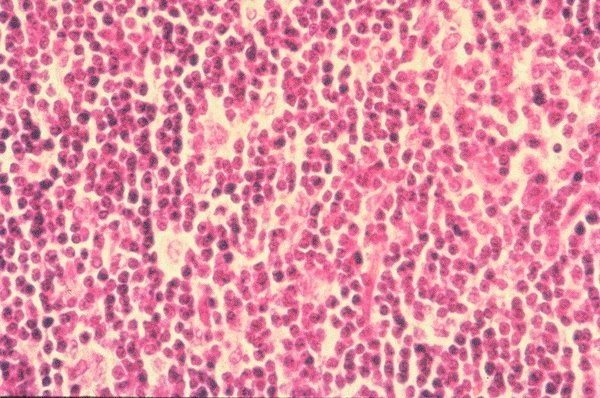

This is a low power view of a lymph node biopsy

and the perifollicular zone which harbors primarily

T cells.